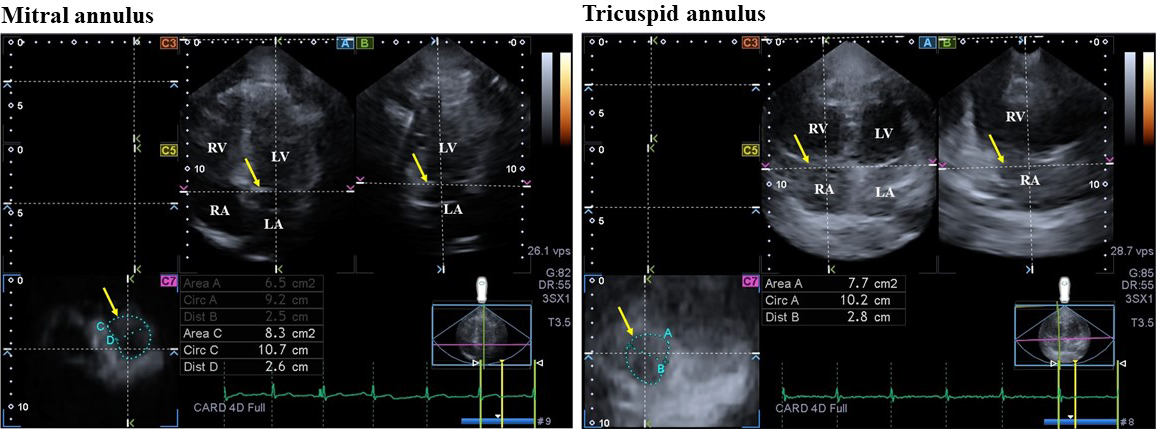

The end-diastole was considered when peak R wave was on electrocardiogram. The end-systole was considered as the first frame when the aortic valve was closed (at the end of T wave on electrocardiogram). MA/TA assessments were made using optimized image planes on the endpoints of the MA/TA on apical two- and four-chamber views and on C7 short-axis view. Several MA/TA measures and features of their function were calculated at end-diastole and at end-systole (Fig. 1) [15, 16]:

Fig. 1.Three-dimensional (3D) echocardiographic assessment of mitral and tricuspid annuli in a patient with hypereosinophilic syndrome. (A) apical four-chamber view, (B) apical two-chamber view and cross-sectional view (C7) of the mitral and tricuspid annuli optimalised on mitral and tricuspid annular images. Yellow arrows indicate plane of the mitral and tricuspid annuli. Abbreviations: Area, mitral/tricuspid annular area; Circ, mitral/tricuspid annular perimeter; Dist, mitral/tricuspid annular diameter; LA, left atrium; LV, left ventricle; RA, right atrium; RV, right ventricle.